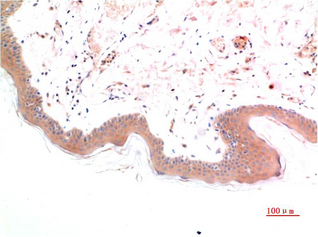

Specificity:SCN3A Polyclonal Antibody detects endogenous levels of protein.

Expression:Expressed in enterochromaffin cells in both colon and small bowel (at protein level).